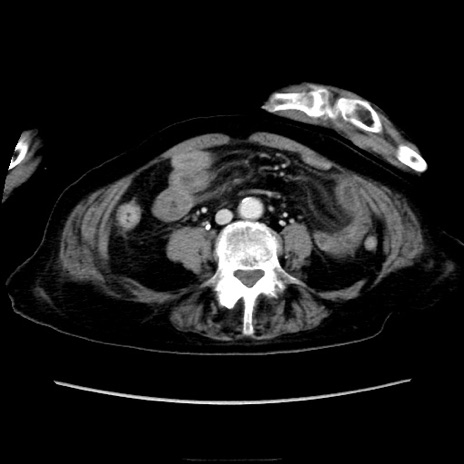

症例40(横断像)

【症例】90歳代女性

【主訴】腹痛・嘔吐

【現病歴】 食欲低下、嘔吐があり昨日他院受診。肺炎と診断され入院となる。入院後より腹部全体に圧痛あり。胃管留置され経過みていたが、症状持続するため、

当院転院となる。

【既往歴】胸椎圧迫骨折、胆石症

【身体所見】腹部:中央に激痛あり、圧痛あり、反跳痛不明

【データ】WBC 17100、CRP 18.82

横断像